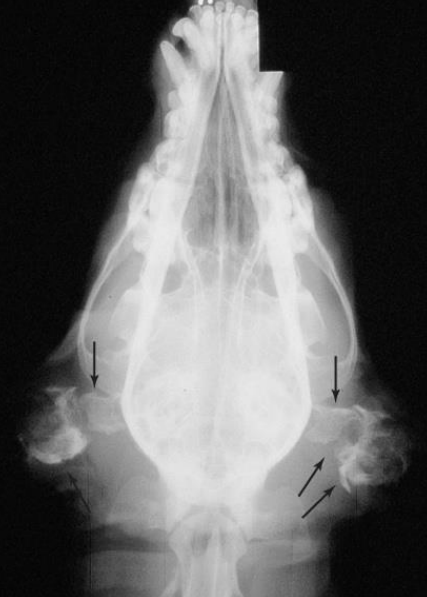

- ๋ฐฉ์ฌ์ , CT : concurrent otitis media, calcification, bone lysis (neoplasia)

์ด๋๊ฐ ๋ผ์ฒ๋ผ ๋ณด์.

์ผ์ชฝ tympanic cavity ๋ ์ ์ / ์ค๋ฅธ์ชฝ์ ๊ฝ ๋งํ ์๊ณ , ๋ผ๋ ์์.

์ค๋ฅธ์ชฝ์ ์ค์ด๋ก ๋์ด๊ฐ๊ธฐ ์ ์ ๋นจ๋ฆฌ ์กฐ์น ํ์ / ์ผ์ชฝ์ ์ค์ด๊น์ง ์ด๋ฏธ ์งํ / ๋๊ทธ๋ผ๋ฏธ๋ petrous temporal bone; lysis๊ฐ ์ผ์ด๋ ๊ฐํต์ฑ ์๋ ๊ฒ์ฒ๋ผ ๋ณด์ - ์ข ์ ์์ฌ